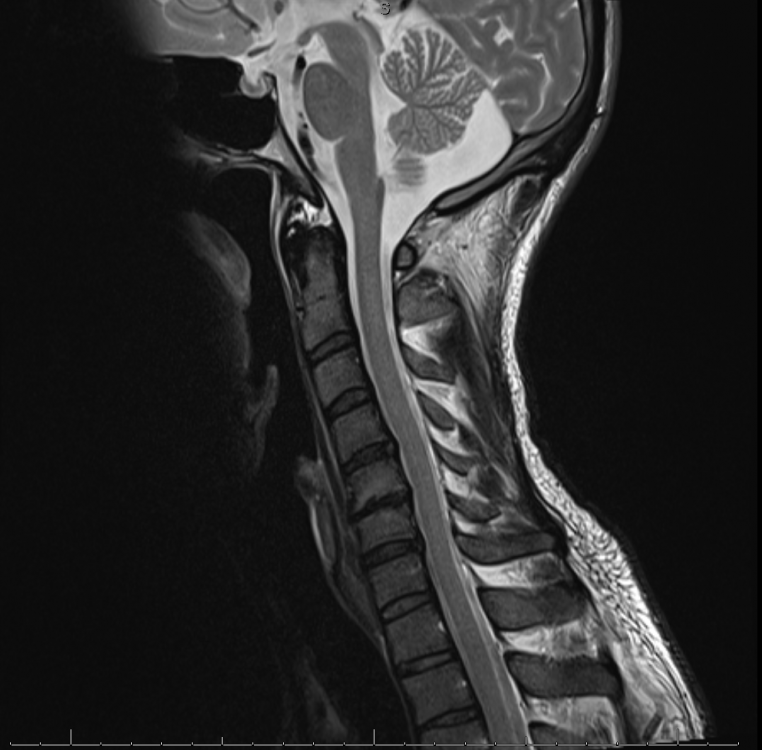

ich habe eine Frage bezüglich meiner Körperhaltung. Ich leide seit fast 5 Jahren an wiederkehrenden brennenden Schmerzen in beiden Händen. Nach einer Odyssee an Arztbesuchen beim Neurolgen, Orthopäden, Heilprakter, Chriopraktier etc. hatte man mich zunächst aufgrund von Arthorse am Handgelenk operiert. Hierdurch stellte sich keinerlei Verbesserung ein und man machte ein MRT der HWS. Hierbei ein breitflächiger Bandscheiben vorfall auf C5/6 und C6/7 ohne Beeinträchtigung der Nervenwurzel sowie eine Steilfehlstellung der HWS und Osteochondose Grad II festgestellt. Infolge dessen habe ich Cortison an die Nervenwurzeln gesprizt bekommen. Ich war dann zunächst 6 Monate komplett symptomfrei. Seit ca. 3 Monaten ist der Schmerz teilweise wieder da, jedoch nicht mehr annähernd so schlimm wie noch vor der Behandlung. Seit einigen Monaten leide ich jedoch zudem, und das ausschließlich im Sitzen, an einem pelzigen Gefühl im Bereich des Nackens sowie beider Schläfen und teilweise im Lippen und Kinnbereich. Sobald ich aufstehe und mich bewege, ist es deutlich besser. Das unangenehme Gefühl stellt sich jedoch relativ schnell ein sofern ich wieder sitzen. Mein Arbeitsplatz wurde bereits ergonomisch angepasst.

Ich weiß aus der Vergangenheit, dass ich eine fehlende Lordose in der LWS, eine fehlende Kyphose in der BWS und eine fehlende Lordose in der HWS habe. Dies wurde vor 2 Jahren auch durch eine Röntgenaufnahme bestätigt. Seit einigen Monaten arbeite ich zudem an der Verbesserung meiner Haltung. Durch meinen Physiotherapeuten wurde mir damals gesagt, ich solle meine Hamstrings sowie den Hüftbeuger dehnen. Seit ich mich jedoch mit der Materie etwas beschäftige, bin ich etwas verwirrt. Meines jetzigen Wissens nach, kommt eine fehlende Lordose in der HWS vor allem durch eine Verkürzung der Beinrückseite sowie des Bauches und einer Inaktivität der Hüftbeuger sowie des unteren Rückens.

Ich habe hier einmal die Röntgenbilder der LWS und BWS sowie den MRT Befund beigefügt. Ich bin mir durchaus bewusst, dass ein fachärztlicher Rat natürlich genau ratsam ist wie eine persönliche Vorstellung bei eben jenem, allerdings war ich wie gesagt, bereits bei etlichen Ärzten und noch möchte ich versuchen, einer künstlichen Bandscheibe aus dem Weg zu gehen.

MRT HWS.png